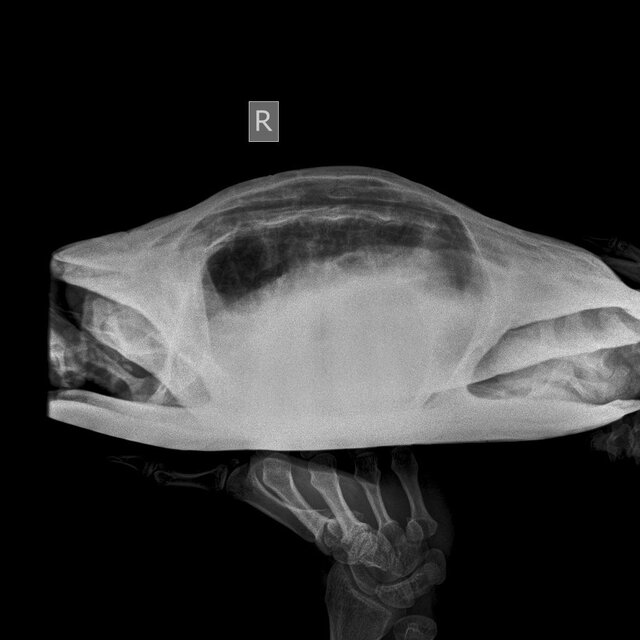

@moth , сделали рентген. Можете по нему что-то сказать?

photo_2023-08-03_20-38-03 (3).jpg

photo_2023-08-03_20-38-03 (2).jpg

photo_2023-08-03_20-38-03.jpg

@MaksimTraper

врач ответила, что возможно отек легких травматического характера и просто капиллярное кровотечение.

В идеале да, сделать кт лёгких, чтобы точно посмотреть. По рентгену криминала нет.